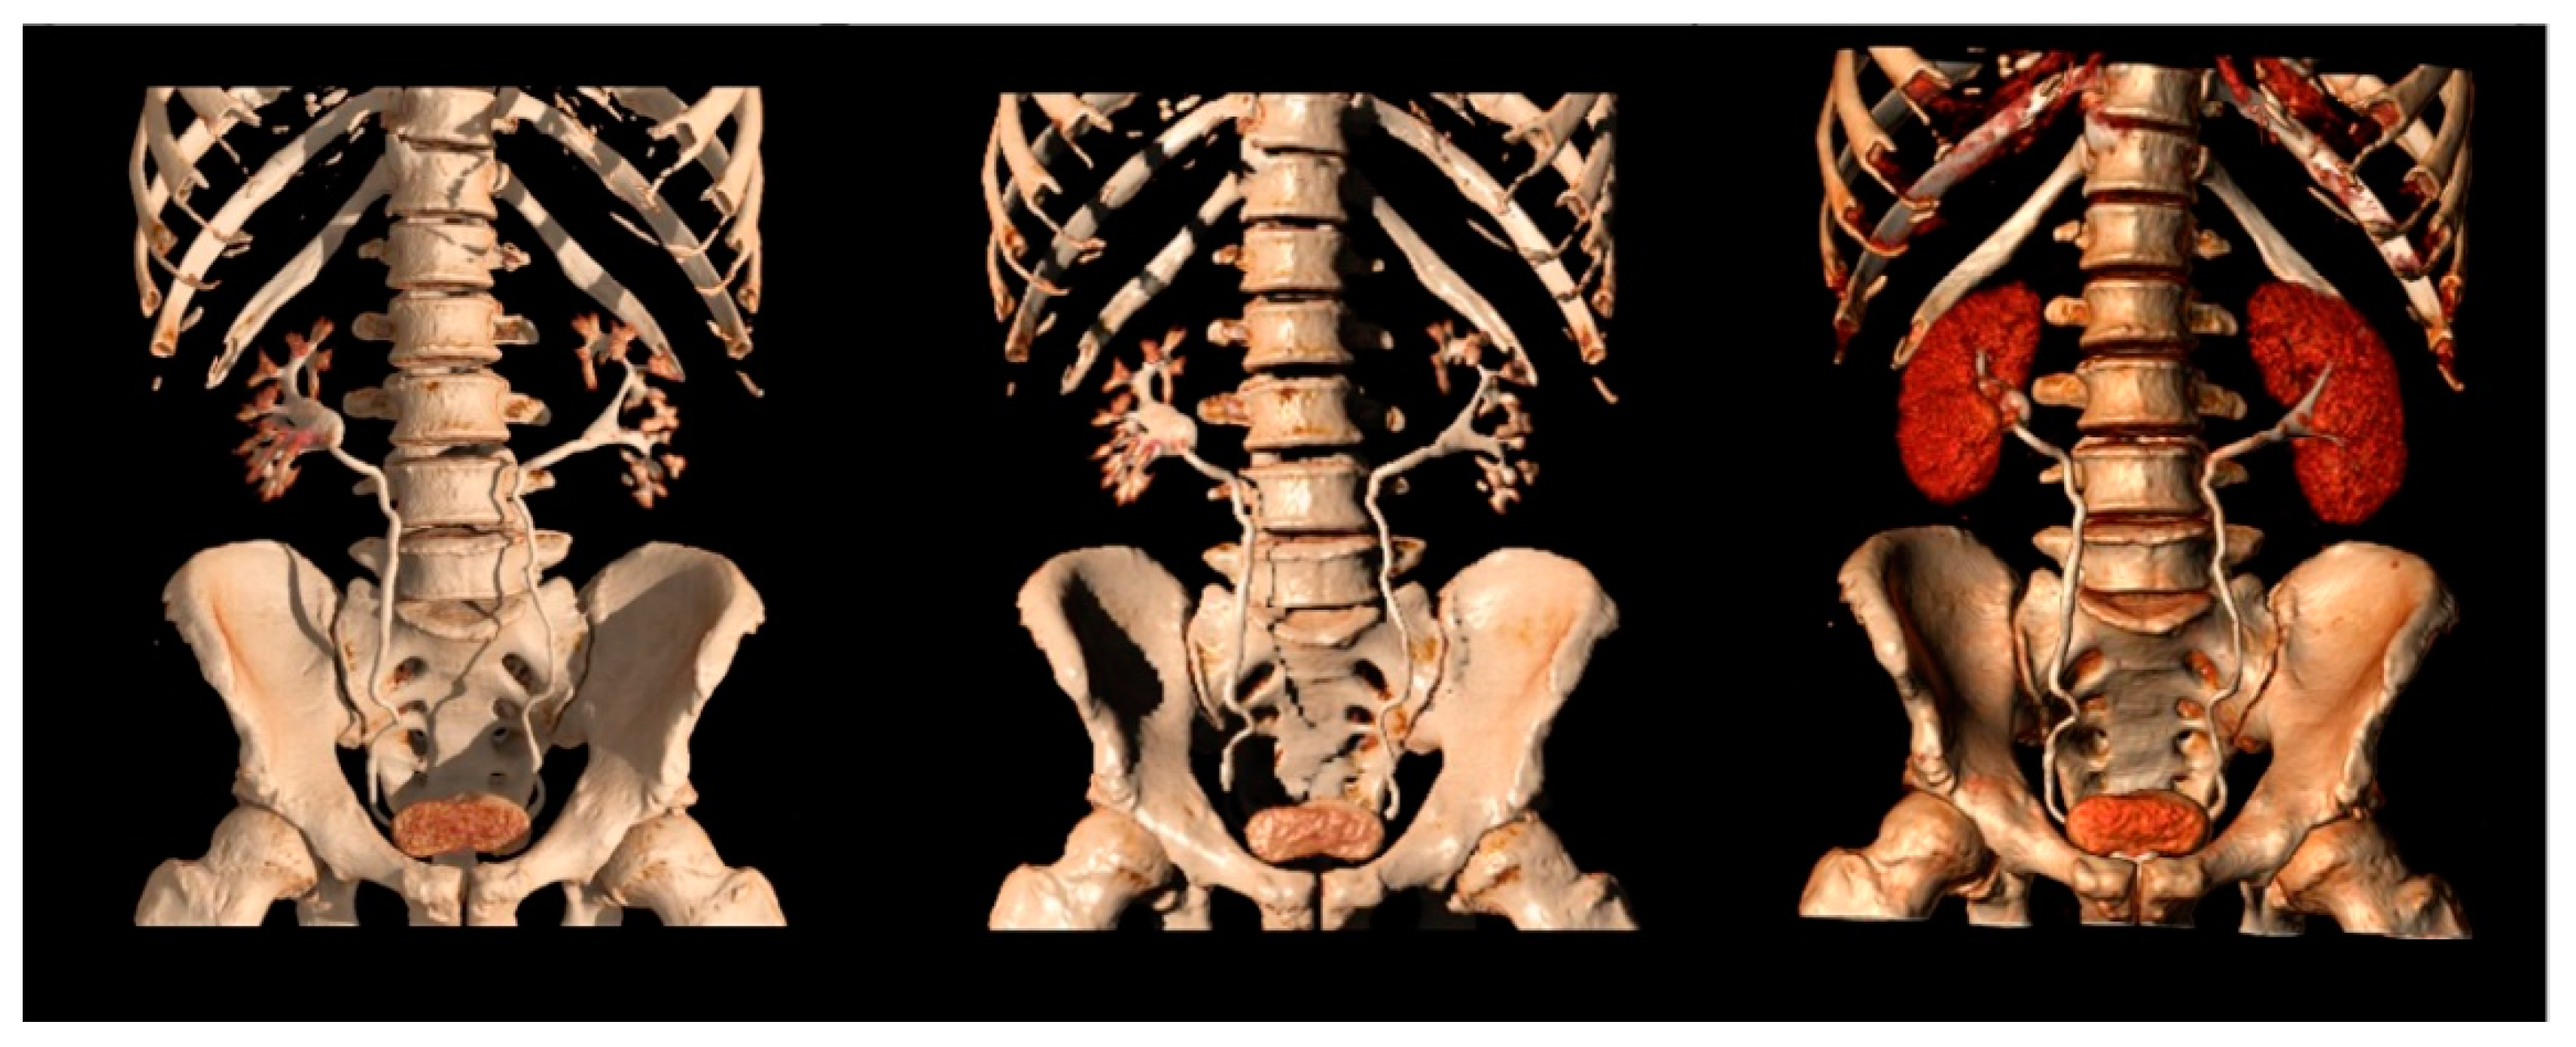

Multiplanar, Maximum Intensity Projection (MIP), and tridimensional volume rendering reconstructions can be performed to increase sensitivity and visualization of the kidneys and urothelium.

Native thin (0.5–0.75 mm) axial images are usually submitted to coronal and sagittal reformations, then further to MIP and 3D reconstructions (Figure 7).

Figure 7.

Different 3D reconstructions of the excretory phase.

MIP reformations are constructed from the highest attenuation voxels in a dataset and projected into a 3D format. These reconstructions are particularly helpful in evaluating the collecting systems and ureters, allowing a complete and quick overview of the high-density contrast within the collecting systems, and highlighting subtle filling defects, focal thickening of the excretory system walls, luminal narrowing or strictures, calyceal abnormalities, hydronephrosis, and hydroureter.

Three-dimensional reconstructions provide specific colors to each voxel in a data set according to its attenuation and relationship to other adjacent voxels, allowing the visualization of the whole opacified excretory system. Some authors support their role in the identification of slight urothelial thickening, especially in cases of reduced excretion of the contrast into the collecting system, when MIP reformations are of limited usefulness [7,19,46].